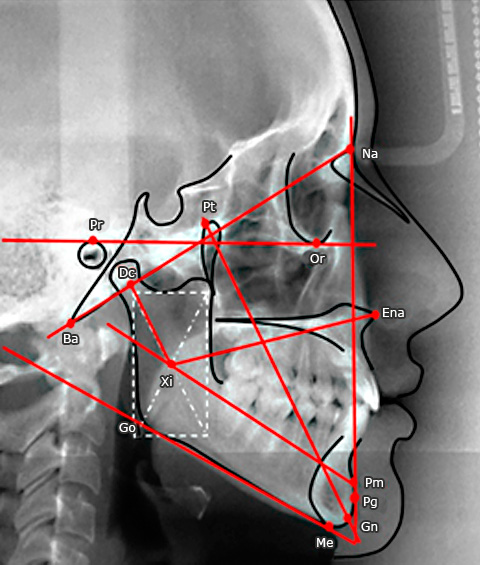

Posterior a ello, el investigador realizó el trazado cefalométrico de las 225 radiografías siguiendo los criterios establecidos por Ricketts(8) ubicando los puntos cefalométricos (N, Po, Or, S), líneas, planos cefalométricos (línea Sella-Nasion, plano horizontal de Frankfort) y ángulos cefalométricos (ángulo entre el plano horizontal de Frankfort y la línea Silla-Nasion). Las radiografías fueron clasificadas de acuerdo con su biotipo facial en dolicofacial, mesofacial y braquifacial empleando el índice de VERT,(14) el cual se obtuvo con la medida de 5 ángulos (Fig.).

El primero es el eje facial, que es el ángulo formado entre el plano eje facial “Pt-Gn” y el plano “Ba-Na”; el segundo es la profundidad facial, que es el ángulo formado entre el plano facial “Na-Pg” y el plano de Frankfort “Po-Or”; el tercero es el ángulo del plano mandibular, que se forma entre el plano mandibular (tangente al borde inferior de la mandíbula) y el plano de Frankfort “Po-Or”; el cuarto es la altura facial inferior, que es el ángulo formado entre la espina nasal anterior “Ena”, el centro de la rama “Xi” y la protuberancia mentoniana “Pm”; y el último es el arco mandibular, que es el ángulo formado entre el eje del cuerpo “Xi-Pm” y el eje condilar “Xi-Dc”.

Fig. - Determinación del biotipo facial según el índice de VERT.